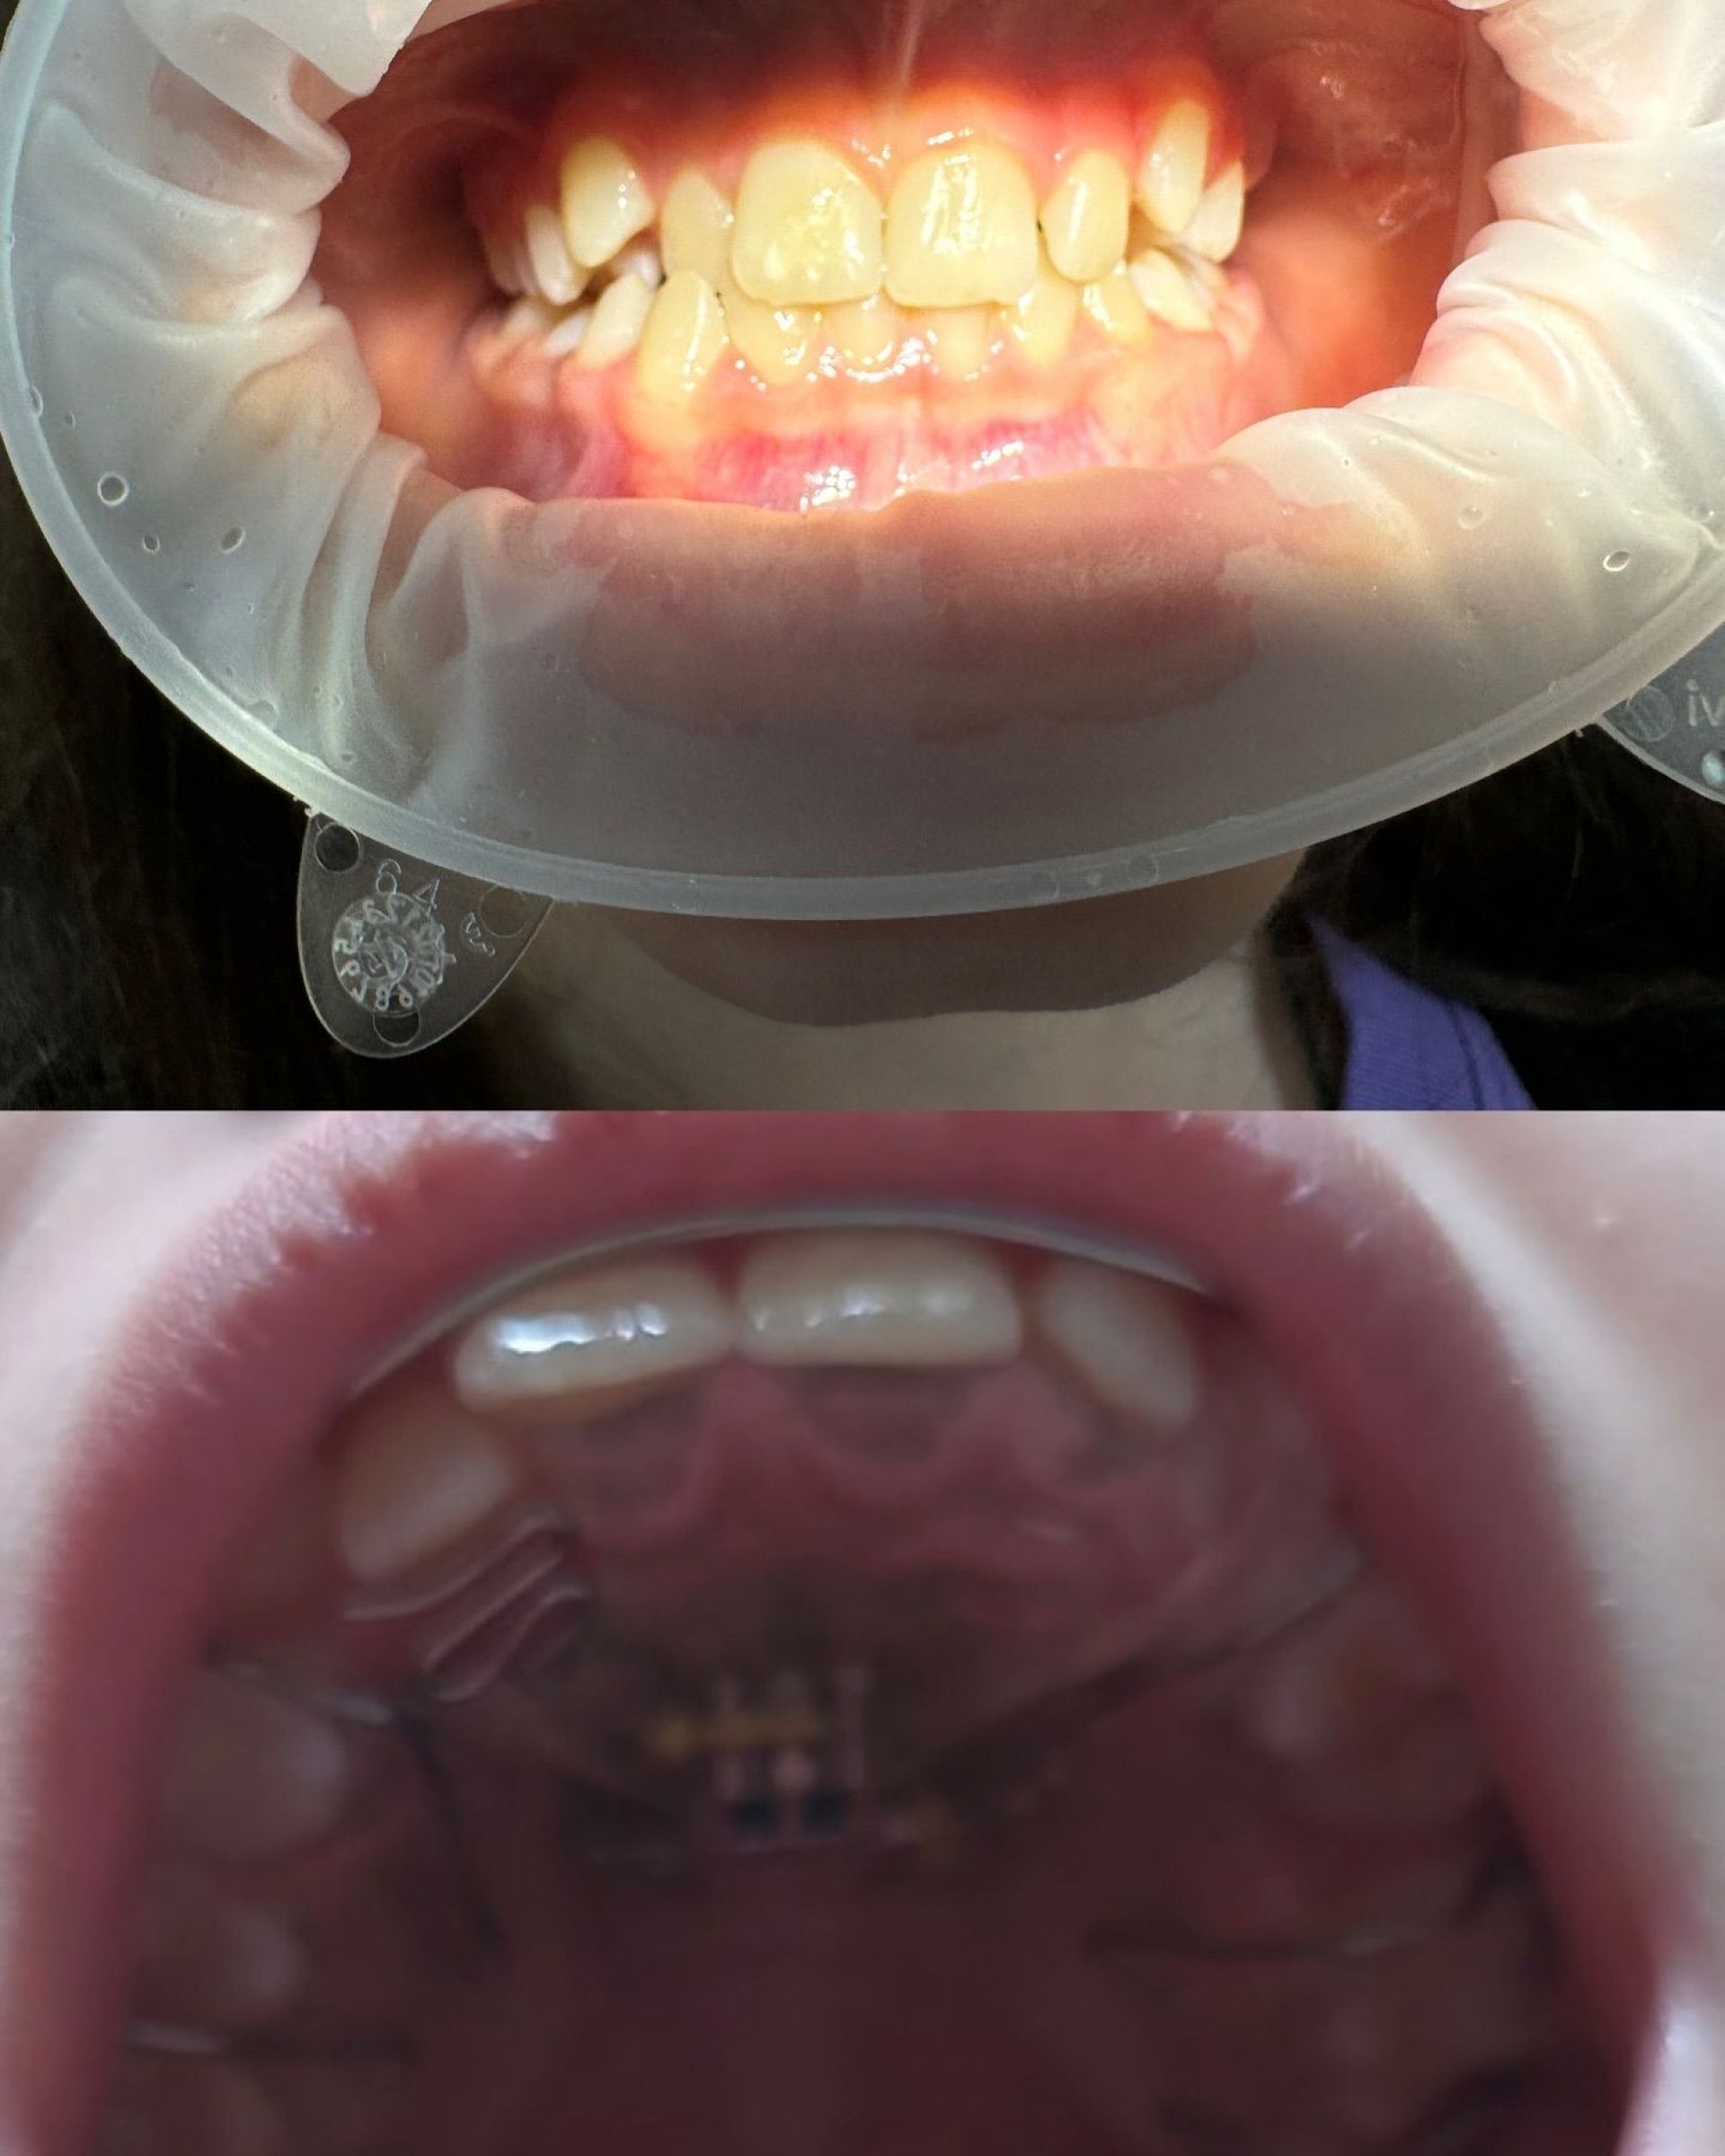

Стоматолог-ортодонт Белінський Владислав

Стоматолог-ортодонт Владислав Андрійович Белінський – це спеціаліст, який надає кваліфіковану стоматологічну допомогу дітям, орієнтуючись на сучасні стандарти якості та безболісне лікування. Він приділяє особливу увагу кожному маленькому пацієнту, створюючи комфортну атмосферу і забезпечуючи ефективне лікування без стресу для дитини.

Лікар-ортодонт допомагає у вирішенні проблем із прикусом та неправильним розміщенням зубів, що є дуже важливим у дитячому віці для формування здорової зубної архітектури в майбутньому. Владислав Андрійович використовує інноваційні методи та сучасні технології для досягнення найкращих результатів.

Для дітей він пропонує встановлення брекетів, елайнерів, пластинок і вінірів, що сприяють правильному формуванню прикусу та зубного ряду. Завдяки індивідуальному підходу кожна дитина отримає найкраще лікування відповідно до її потреб.

- Встановлення брекетів, елайнерів, пластинок.